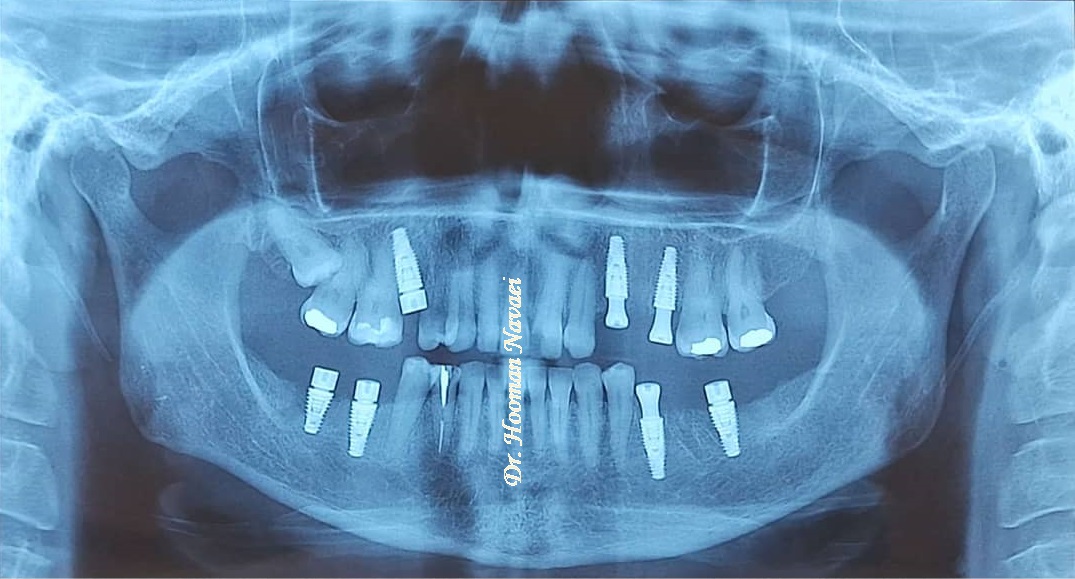

• چند دندان از دست رفته: برای پشتیبانی از دندان مصنوعی یا بریج‌های جزئی ثابت، در زمانی که چندین دندان وجود ندارد.

• فک بی‌دندان: زمانی‌که تمام دندان‌های شخص از دست رفته‌باشد، برای تکیه دادن پروتزهای تمام قوس، از ایمپلنت استفاده می‌گردد. این روش در مقایسه با دندان مصنوعی معمولی، پایداری را بهبود می‌بخشد. منظور از پروتزهای تمام قوس، بریج‌های هیبریدی ثابت یا اوردنچرهای متکی بر ایمپلنت (implant-supported overdentures) می‌باشد.